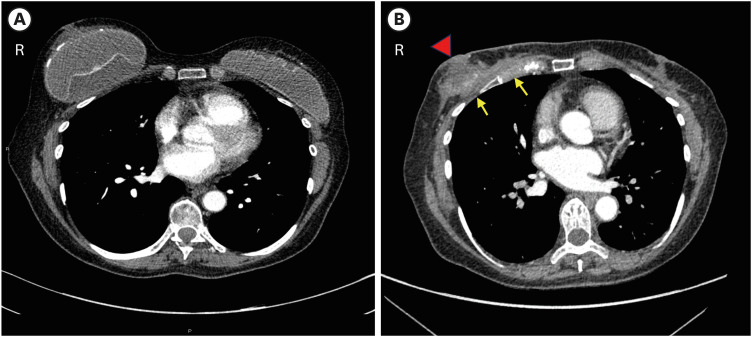

Breast implant augmentation is a low-risk procedure with few life-threatening complications, most commonly rupture or leakage and contraction of the capsule. Breast implant-associated (BIA) malignancies are rare. Anaplastic large cell lymphoma (ALCL) is the most well-known neoplastic condition associated with breast augmentation. Carcinomas arising in association with implants have been reported but are rarer than ALCL. BIA-mesenchymal tumors are extremely rare and most are locally aggressive fibromatosis. To date, only eight cases of BIA sarcomas have been reported. Herein, we describe a case of silicone BIA-undifferentiated pleomorphic sarcoma (UPS) that was initially mistaken for ALCL because of a significant clinical and radiological overlap in presentation and imaging. Here, we present the morphological and molecular features of this rare neoplasm. We reviewed the existing literature related to BIA sarcomas to highlight the importance of considering this diagnosis in cases of recurrent ALCL-negative BIA effusions.